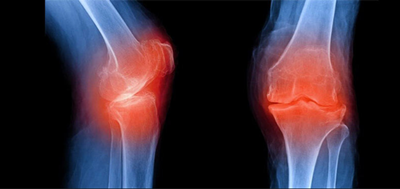

전문가들은 무엇이 퇴행성 관절염을 유발하는지 또는 왜 조직의 분해가 시작되는 아직 정확히 확인된바는 없다고 말하고 있습니다. 그러나 일단 이 상태가 진행되기 시작하면 관절의 다양한 부분을 손상시킬 수 있습니다. 연골, 힘줄과 인대, 뼈, 무릎 주변등의 손상이 진행될 수 있습니다.

관절 손상이 진행되면 관절 통증과 붓기, 운동 범위 감소 등이 발생하게 되고 통증이 시작되면, 시간이 지남에 따라 근육이 약해져 활동성이 현저히 떨어질 수 있습니다. 약한 근육은 관절을 지탱하지 못하고 결국 영향을 받은 관절은 변형이 될수 있습니다.

흔히 골관절염 또는 마모성 관절염으로 불리는 퇴행성 관절염은 시간이 지나면서 그리고 사람들이 나이가 들면서 뼈의 끝에 있는 보호 연골은 점차 닳아 없어 집니다.

특히 퇴행성관절염은 주로 무릎, 엉덩이, 척추, 그리고 손에도 그 영향을 미칩니다. 기계도 오래 사용하면 닳듯이 사람 몸의 관절도 오래 사용하고 무리하게 사용하게 되면 보다 더 일찍 닳게 됩니다. 관절 손상은 되돌릴 수 없습니다. 하여 평소 건강한 체중을 유지하고 예방하는 활동을 통해 더 오래 삶의 질을 잘 유지하는 것이 지혜로운 삶이 될 것입니다.